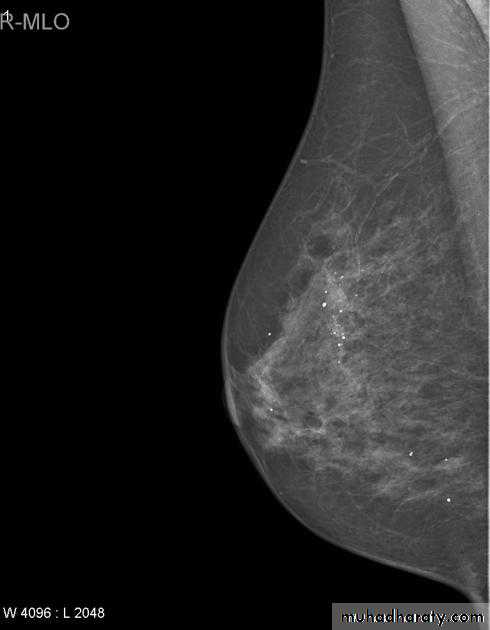

Mammography views

The mediolateral oblique (MLO) view is one of standard mammographic views. It is the most important projection as it allows to depict most breast tissue.

The craniocaudal view (CC view), is one of the two standard projections in a screening mammography. It must show the medial part as well the external lateral portion of the breast as much as possible.